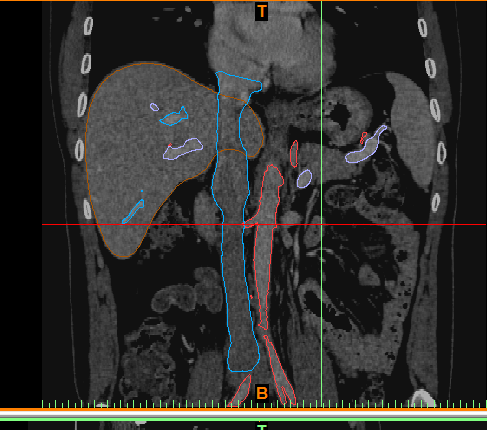

最后建模出来的效果:

正面图(肝脏+动脉+门静脉+腔静脉)                                反面图                                                          透视图

三种视图: